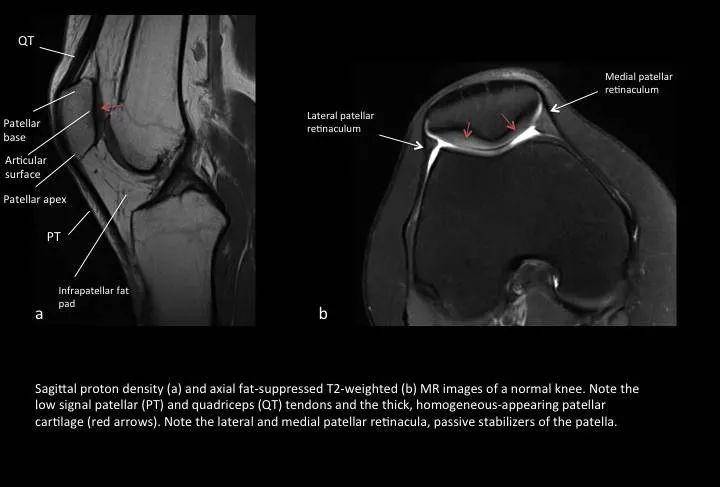

Fig. 2: Normal MR images

图2:正常膝关节MR图像